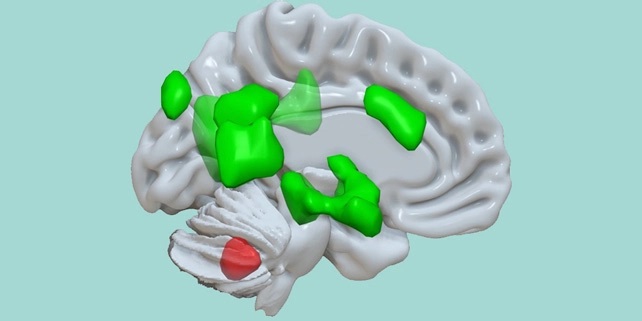

Нещо повече – изследователите установяват, че съществува много по-голямо ниво на общуване между малкия и главния мозък. Малкият получава информация от предния цингуларен гирус, който е отговорен за голяма част от когнитивните функции, сред които емоциите, регулиране на настроението и вземането на решения. Освен това предава информация към бадемовидното тяло и амоновия рог.

Малкият мозък (активация в червено) се свързва с различни части на главния (активации в зелено), за да подобри съхранението на емоционална информация. Източник: MCN/University of Basel.

„Тези резултати показват, че малкият мозък представлява ключов компонент от мрежата, отговорна за по-доброто съхранение на емоционална информация“, казва невроученът Доминик дьо Карван от Базелския университет в Швейцария.